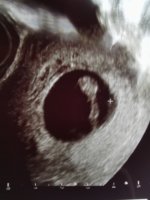

Wow! Gratulerer! To sett med tvillinger i gruppa så langtDa har jeg også vært på tul! Her var det to bankende hjerterVar egentlig litt forberedt da vi satte tilbake to blastoer (ivf) men allikevel et sjokk! Det nederste var litt mindre enn det andre 4 og 7 mm. Så litt usikkert hvordan det blir, ny ultralyd om en uke

målt til 5+5, satt en uke tilbake. Fikk se bankende hjerte